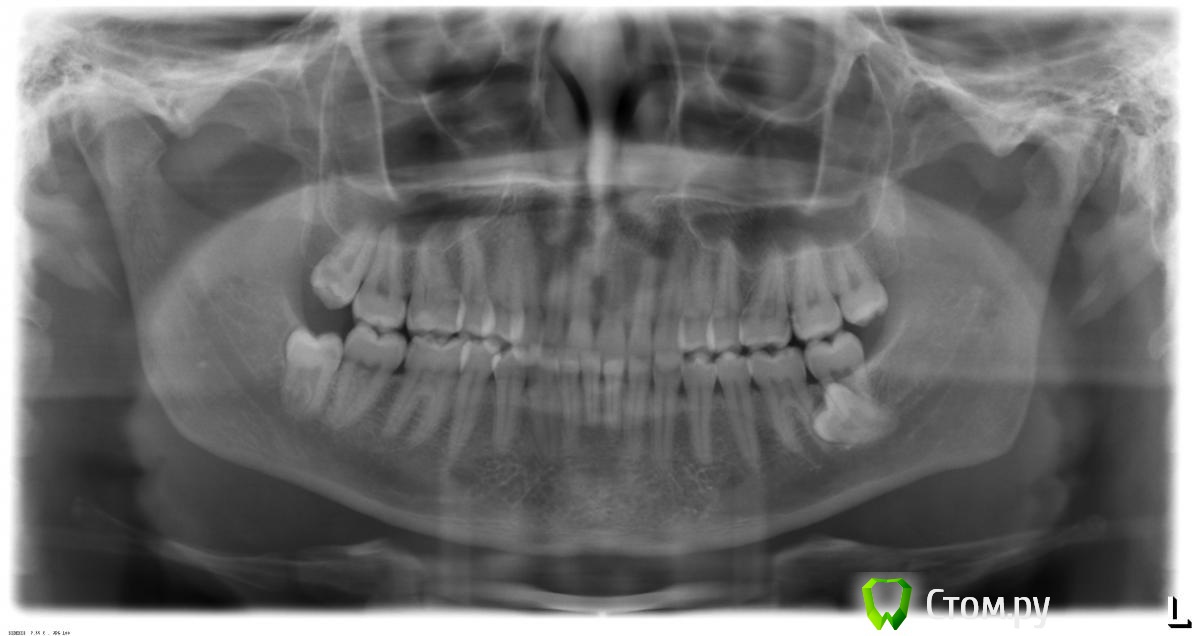

DenisF Опубликовано 15 августа, 2014 Поделиться Опубликовано 15 августа, 2014 (изменено) Уважаемые доктора! Очень прошу вас поделиться мнением. Изначально обратился ввиду проблем с суставом, но после ортопантомограммы, понял, что проблема суставов далеко не единственная. Пожалуйста, посмотрите ортопантомограмму в прикрепленном файле. Очень смущает восьмерка, которая размещена чуть ли не в горизонтальном положении. Сказали, что при удалении даже возможно потребуется костная пластика. Также, смутило, что не просматриваются корни нижних средних резцов. Заранее благодарю за помощь и уделенное время и внимание! Приятного всем дня! Изменено 15 августа, 2014 пользователем DenisF Ссылка на комментарий

faity Опубликовано 15 августа, 2014 Поделиться Опубликовано 15 августа, 2014 (изменено) я прям моральное удовлетворение получил от вида восьмерки! удалять только с КТ.с корнями все нормально, резорбции не отмечается Изменено 15 августа, 2014 пользователем faity 2 Ссылка на комментарий

red_butler Опубликовано 15 августа, 2014 Поделиться Опубликовано 15 августа, 2014 для начала сделайте Кт, остальное дело техники. я прям моральное удовлетворение получил от вида восьмерки! у меня тоже руки зачесались Также, смутило, что не просматриваются корни нижних средних резцов. \все с ними нормально Ссылка на комментарий